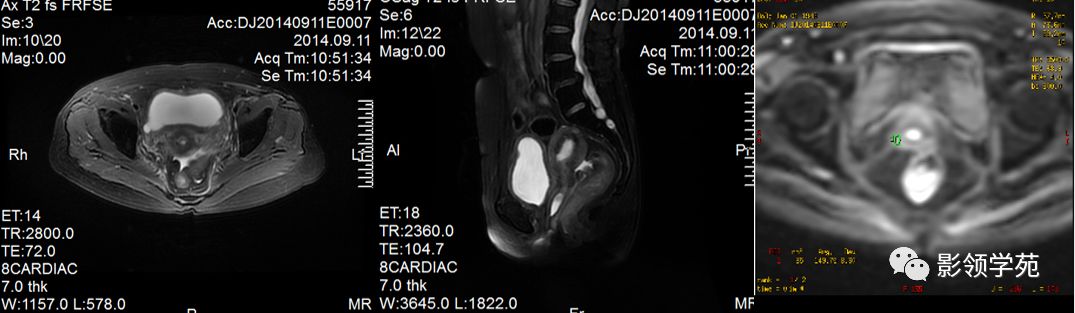

宫颈癌MRI表现

宫颈癌可表现为类圆形或不规则形肿块,在T2WI上表现为均匀或欠均匀的高信号,与正常宫颈基质及宫旁脂肪形成良好的自然对比。

MRI

- Ⅰ期肿瘤:侵犯宫颈基质,T2WI等信号肿块,宫颈管扩大及宫颈纤维基质中断

- Ⅱ期肿瘤:宫颈增大,宫旁肿块或宫旁脂肪组织内出现异常信号的粗线状影

- Ⅲ期肿瘤:侵犯至阴道下部,外延至盆壁,或出现肾积水。

- Ⅳ期肿瘤:膀胱壁或直肠壁低信号中断,膀胱壁或直肠壁增厚或腔内肿块。

DWI:局限性高信号,癌组织ADC值<癌旁组织<小于正常宫颈组织

IIA期

IIB期